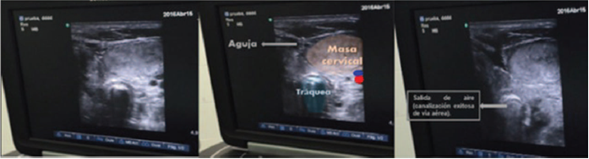

Upon initiation of the procedure, the surgeon was unable to localize the trachea to perform the percutaneous approach, so the anesthesia team proposed the option of using ultrasound guidance to identify the trachea and perform the puncture. The anesthetist proceeded to localize the trachea under ultrasound guidance using the linear transducer of a SonoSite machine. When the trachea had been localized and the other anatomical structures had been identified, the TRACOE kit was opened, and the head and neck surgeon performed an ultrasound-guided puncture in the transverse plane (Fig. 3) using a #14G catheter and secured the airway on the first attempt, with no complications. The metal guide wire was then advanced smoothly, the opening was progressively dilated with the help of a dilator, and a #7.5 cannula was introduced (Fig. 4), confirming correct placement by means of capnography.